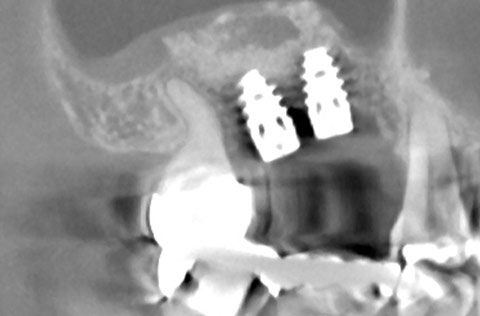

他院でインプラント治療を断られたケース。当院の「ラテラルスリット法」で骨造成を行い、インプラントを埋入できた。